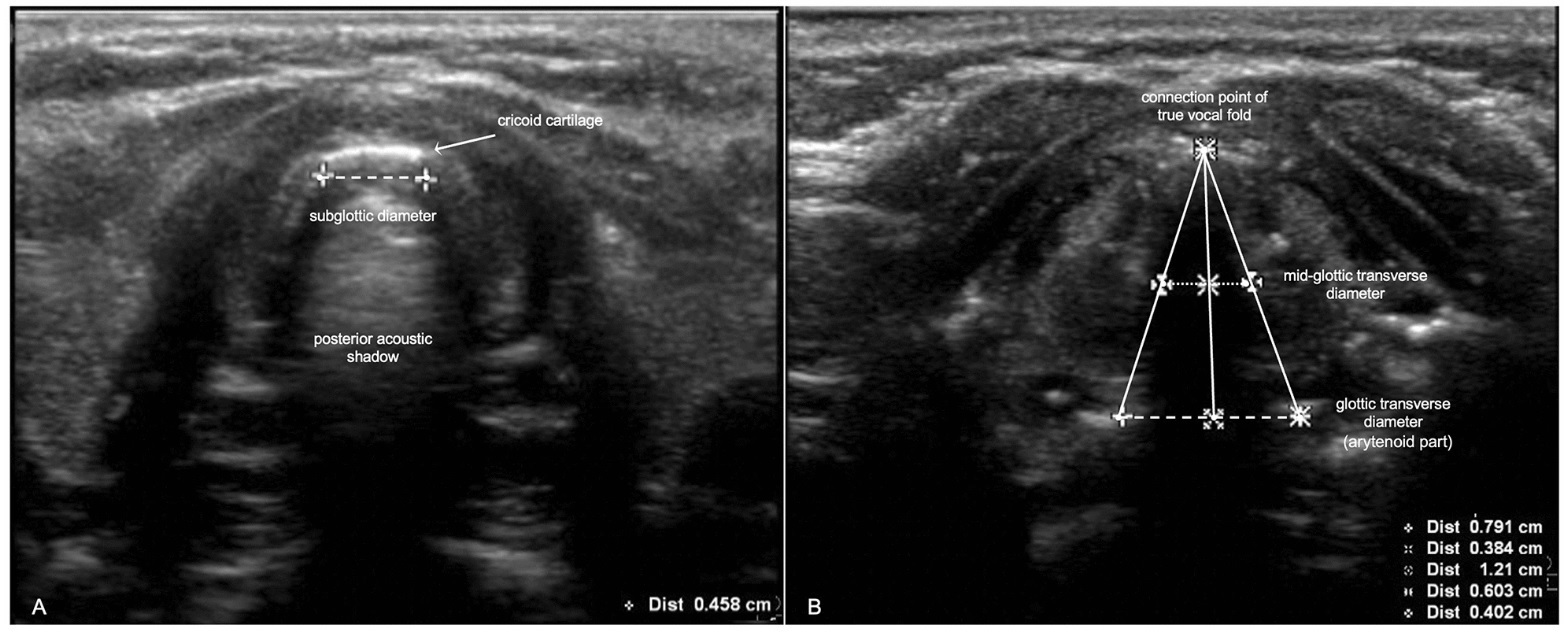

اندازه گیری سونوگرافی قطر عرضی گلوت و قطر ساب گلوت برای پیش بینی اندازه لوله داخل تراشه در کودکان: یک مطالعه کوهورت آینده نگر

Ultrasonography measurement of glottic transverse diameter and subglottic diameter to predict endotracheal tube size in children: a prospective cohort studyاندازه گیری سونوگرافی قطر عرضی گلوت و قطر ساب گلوت برای پیش بینی اندازه لوله داخل تراشه در کودکان: یک مطالعه کوهورت آینده نگر